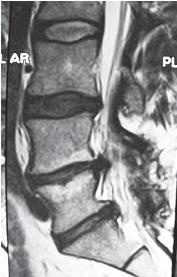

Следующий пример показывает состояние поясничного отдела позвоночника через два года после проведённой ламинэктомии. Ламинэктомия (лат. lamina — пластинка, греч. ektome — иссечение) — хирургическая операция: вскрытие позвоночного канала путём удаления дуг позвонков.

МРТ № 103

На МРТ №°103 наблюдается грыжа межпозвонкового диска в сегменте LIV-LV, частично компенсированная спондилёзом, гипертрофия задней продольной связки и выраженный эпидурит на данном уровне. В сегменте LV-SI наблюдается протрузия межпозвонкового диска, компенсированная спондилёзом. На уровне этих же сегментов наблюдается рубцовоспаечный процесс, как следствие перенесённой хирургической операции — ламинэктомии, проведённой в сегментах (LIV-LV, LV-SI), с целью устранения грыжи межпозвонковых дисков и декомпрессии спинномозговых корешков на данных уровнях.